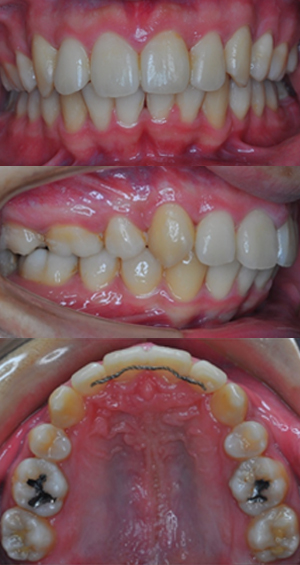

| 主訴 | 出っ歯、乱くい歯が気になる |

|---|---|

| 診断 | 上顎前突 |

| 治療内容 | 上顎左右4番抜歯 マルチブラケット法(BHQH1年間装着後、DBS2年半) |

| 治療期間 | 2年6か月 |

| 治療金額 |

|

| 開始年齢 | 22歳1か月 |

| リスク副作用 | 矯正中は、ブラッシングが不十分だと、虫歯や歯肉炎になるリスクがあります。 また、治療中は治療に対する患者さん自身の協力が必須です。 上下顎前歯の後方移動量が大きくなると、歯の根が短くなる現象が起こる場合があります。また、顎の構造等により前歯の後方移動が制限されることがあります。 治療後の保定管理を怠ると、後戻りが起こりやすくなるため、その後の管理も必要です。 |